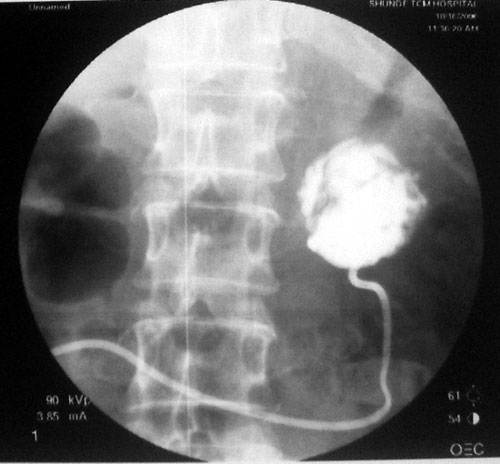

参照ct片,经皮穿刺,抽出透明液体60ml,随后置入引流管引流,囊液细胞学检查阴性,胰酶检查阴性。采用无水乙醇灌注治疗。4天后囊腔闭锁,无液体渗出,予以拔管。

置管后造影,显示囊腔直径约5cm,囊壁光整,正位、双斜位造影均未见造影剂外溢,与胰腺无交通